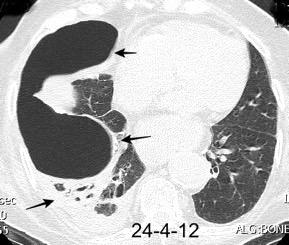

VIH+. 1 mes antes derrame pleural en el curso de una

infección